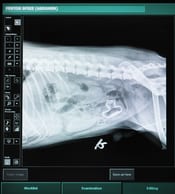

Confirming Foreign-Object Blockage

The veterinarian will give the animal a clinical examination. Feeling the abdomen may be sufficient to determine if there is a blockage. Otherwise, to confirm or determine the presence of a blockage, the following tests may be performed:

• X-rays